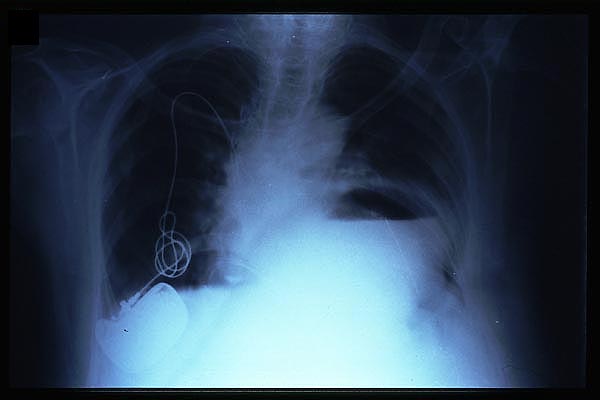

Marcapasos